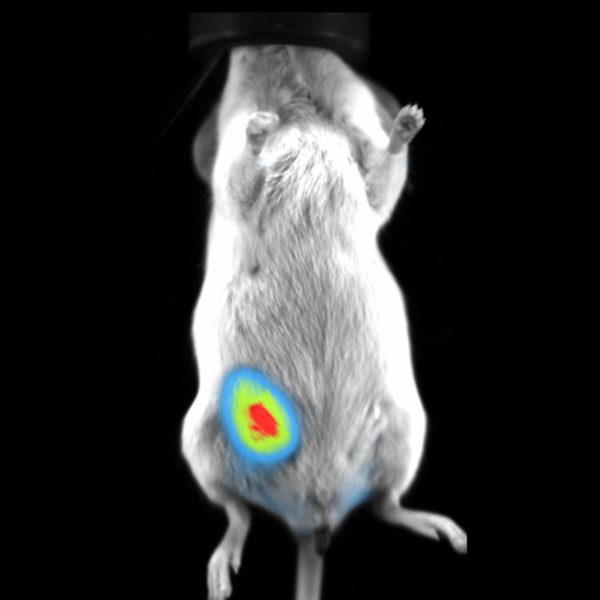

Fluorescence imaging

Vilber's dynamic range of emission filters can be employed in fluorescence imaging to identify fluorescent reporter genes or dyes in vivo.

Subcutaneous tumor expressing mCherry. Image Credit: Scintica Instrumentation Inc